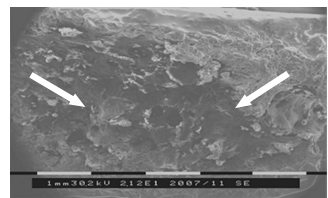

. Исследования тонкой структуры костного матрикса пластинчатых и

трубчатых костей в норме методом сканирующей электронной микроскопии (10

. Исследование морфологии огнестрельных переломов пластинчатых и

трубчатых костей методом сканирующей электронной микроскопии (50 образцов).